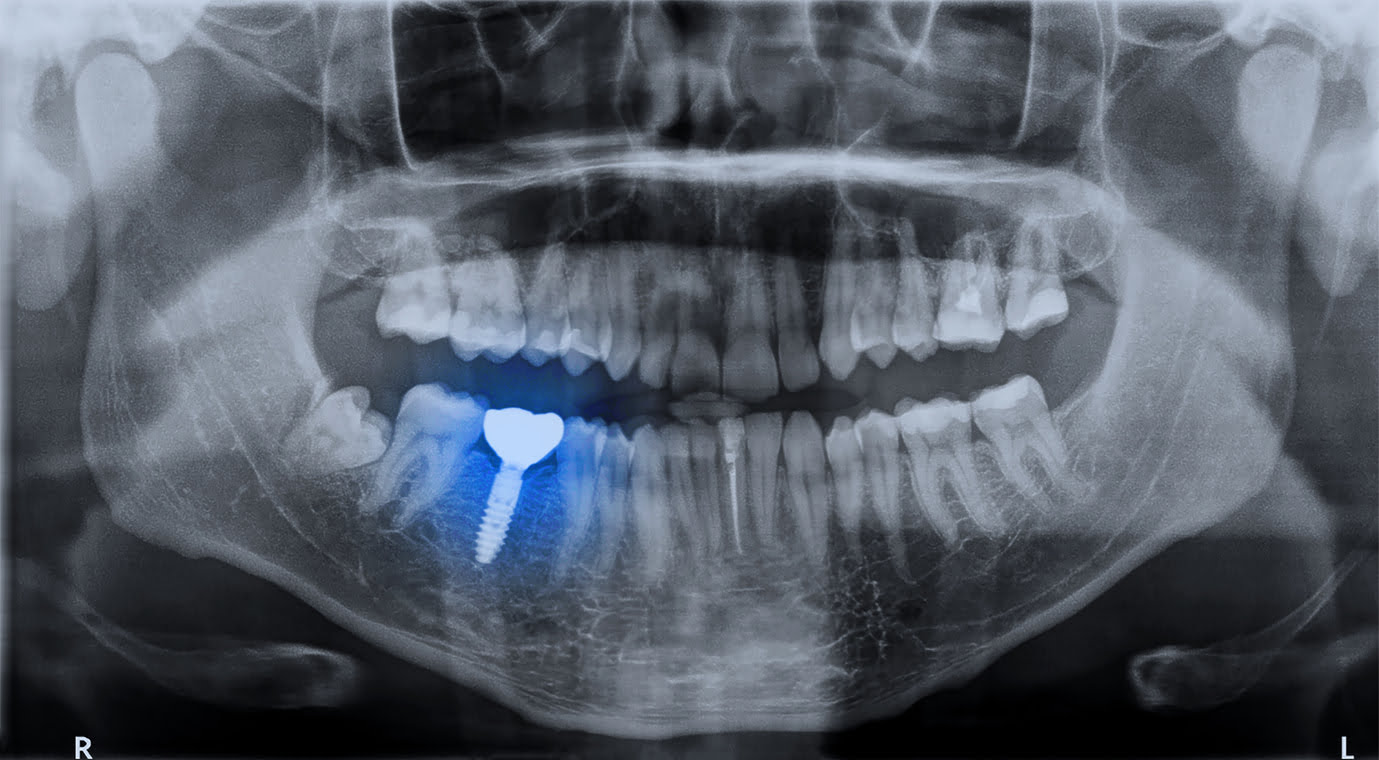

We use advanced digital technology to carefully plan your treatment. State-of-the-art digital scans and images help us accurately work out the best placement for your implant(s) and allow us to predict and manage any potential issues.

The titanium implant is placed into your jawbone during an in-surgery appointment. We use local anaesthetic to minimise any discomfort, and ensure you feel relaxed before we begin. Once fitted, the implant will take 3-6 months to heal and bond with your bone, so we place a temporary tooth to protect your gum as your implants heals.